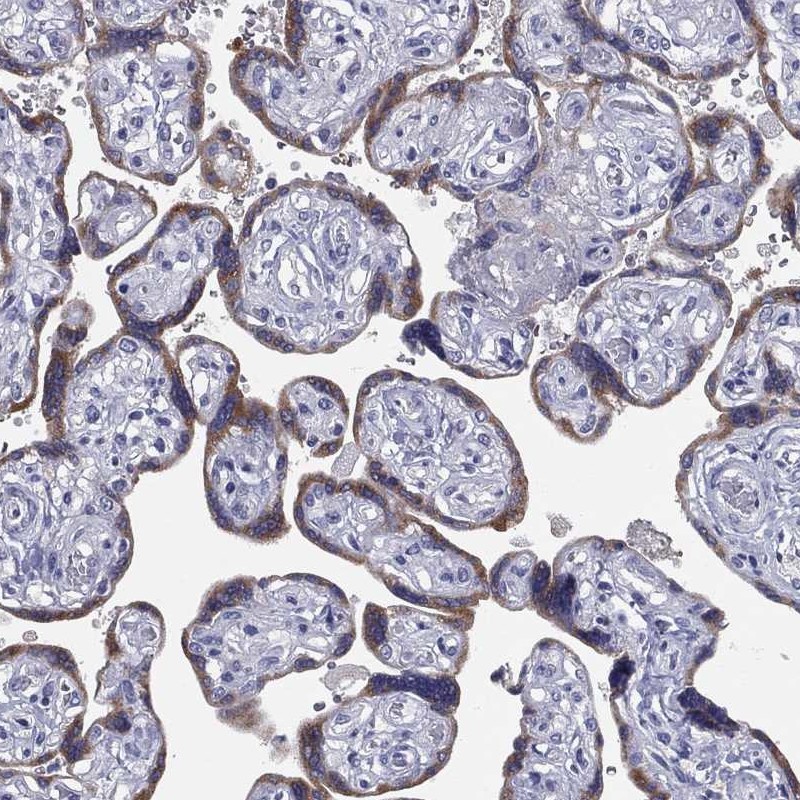

Immunohistochemical staining of human placenta shows moderate cytoplasmic positivity in trophoblastic cells.